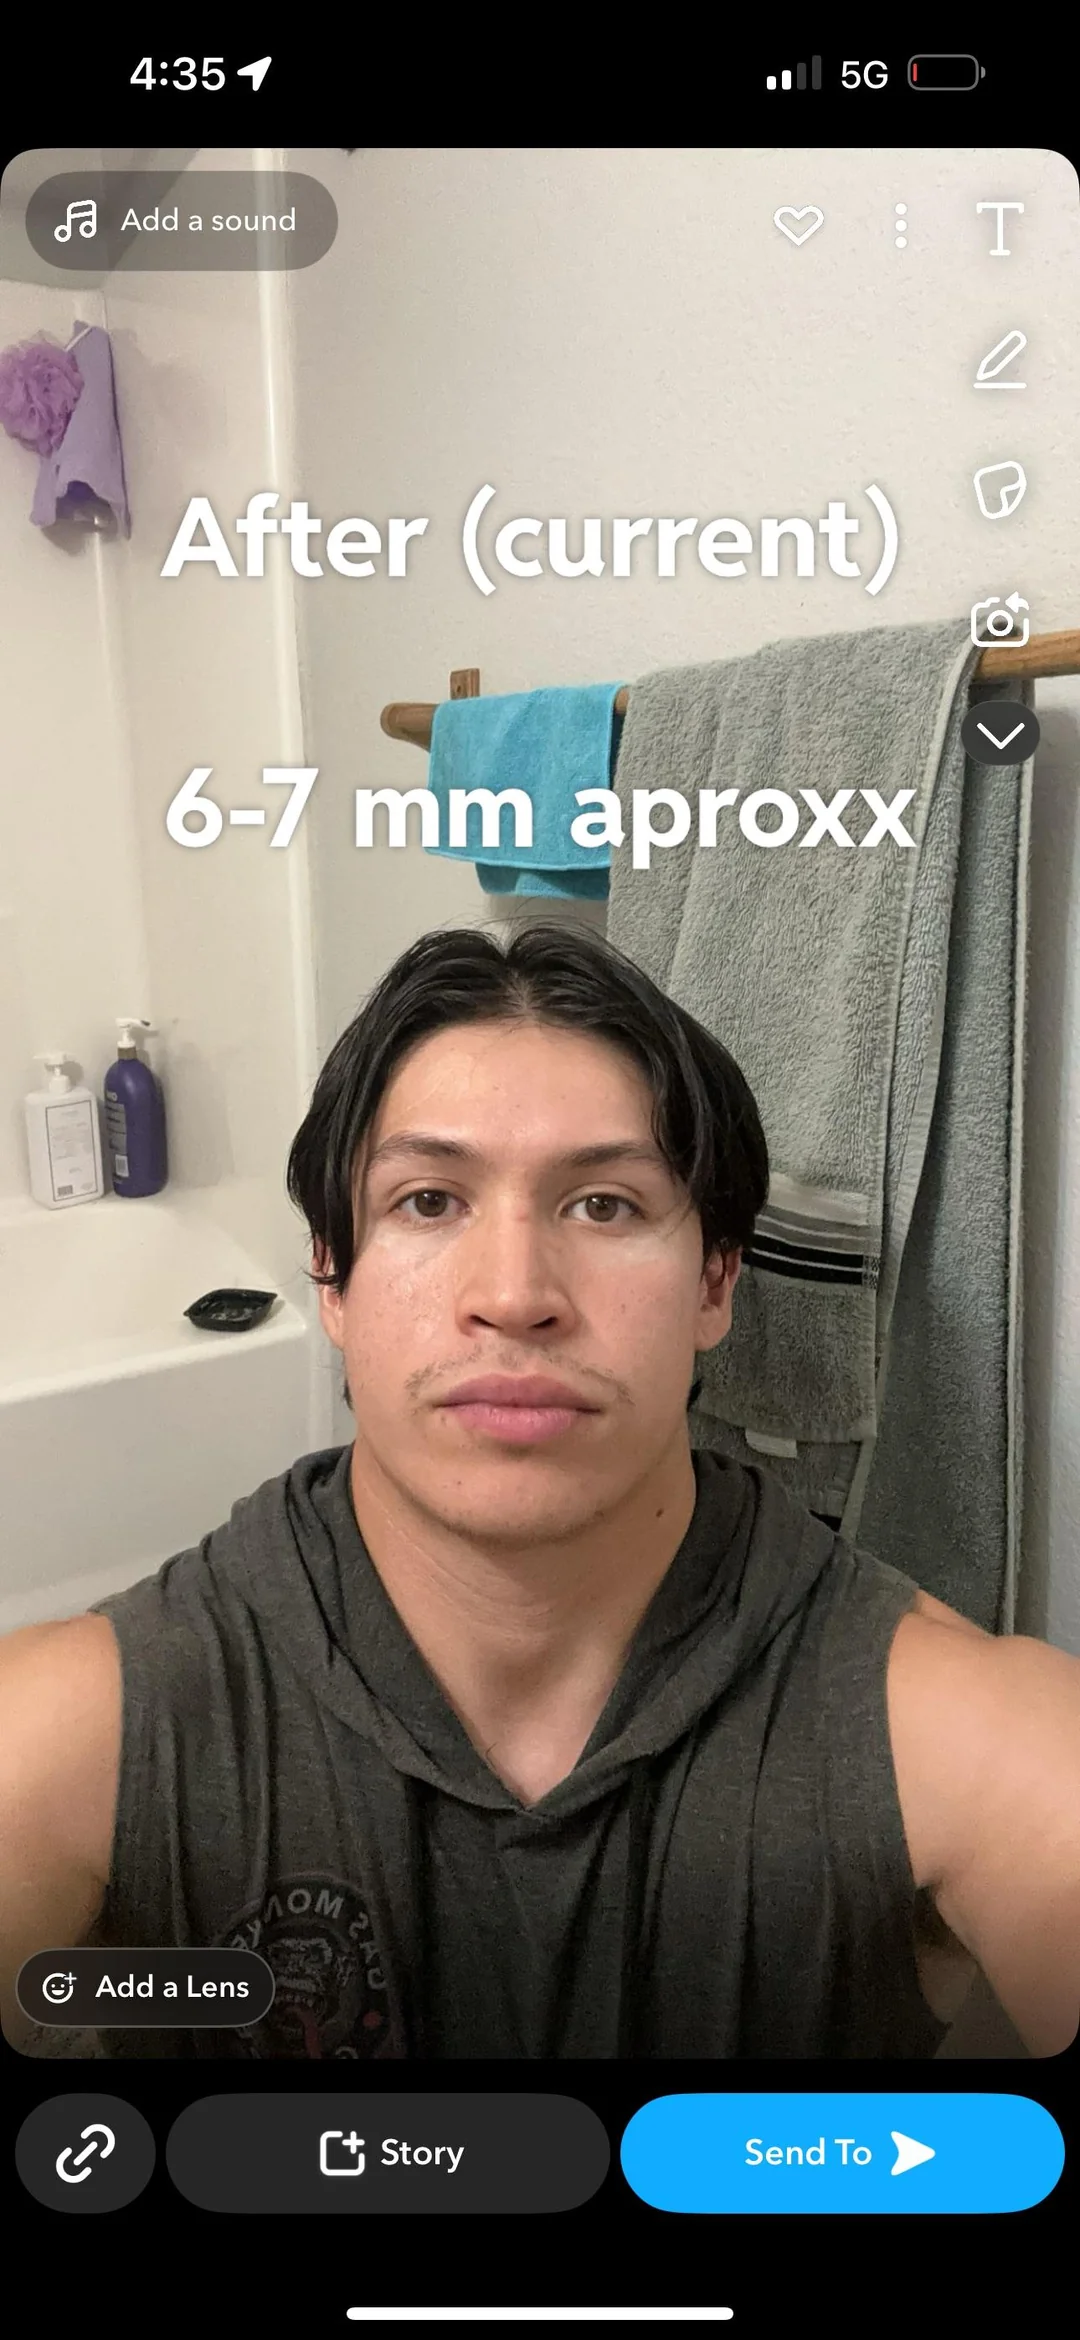

I seriously need help, I want my midface to look broader, but he keeps on saying my palate isn’t narrow, and keep saying the maxilla’s growth spurt ends at 14, so if I can persuade him I would be more than grateful.